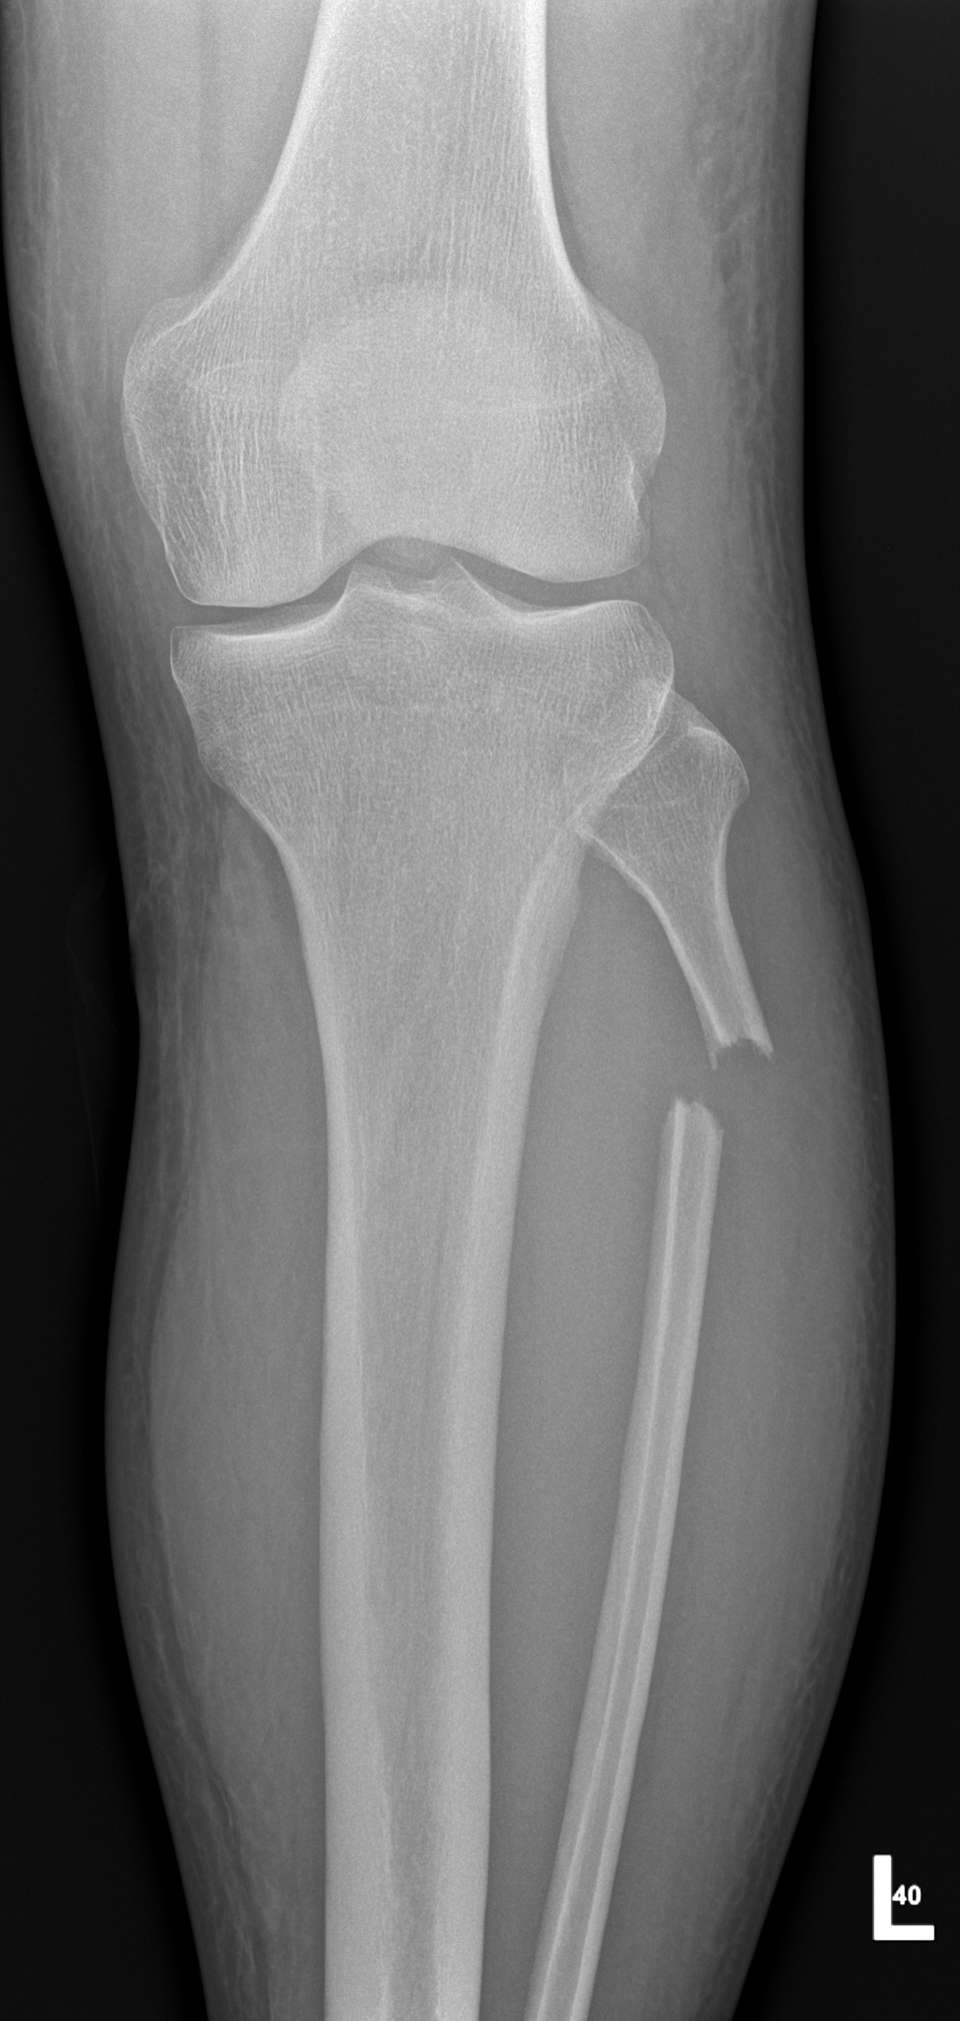

The Rugged Rides 6/24/2022The heart vibrates. 4 months ago my world changed, suddenly and brutally. A nightmare we never want to think of, dark and cold, got me. We were almost finishing a day, one of the first great trips, I was leading. Suddenly the world switched off, and I woke up in the hospital's ED. Despite extraordinary caution, despite years of experience. But how? I was looking in the mirror, I had my blinker on, I slowed down. This time it was not enough. A car surprised me from behind, overtaking us greedily, at a road intersection, against traffic, on a double continuous line. It slammed right into my sideway.